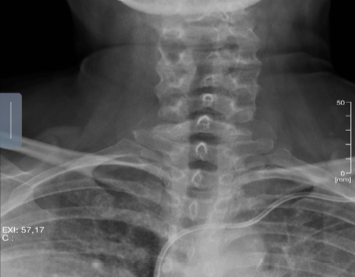

AP lateral x-rays of the cervical spine pertinent for disc degeneration at C5-C6 with minimal facet arthrosis and spondylolysis. Adequate cervical lordosis and no signs of focal kyphosis (Figures 1 & 2).